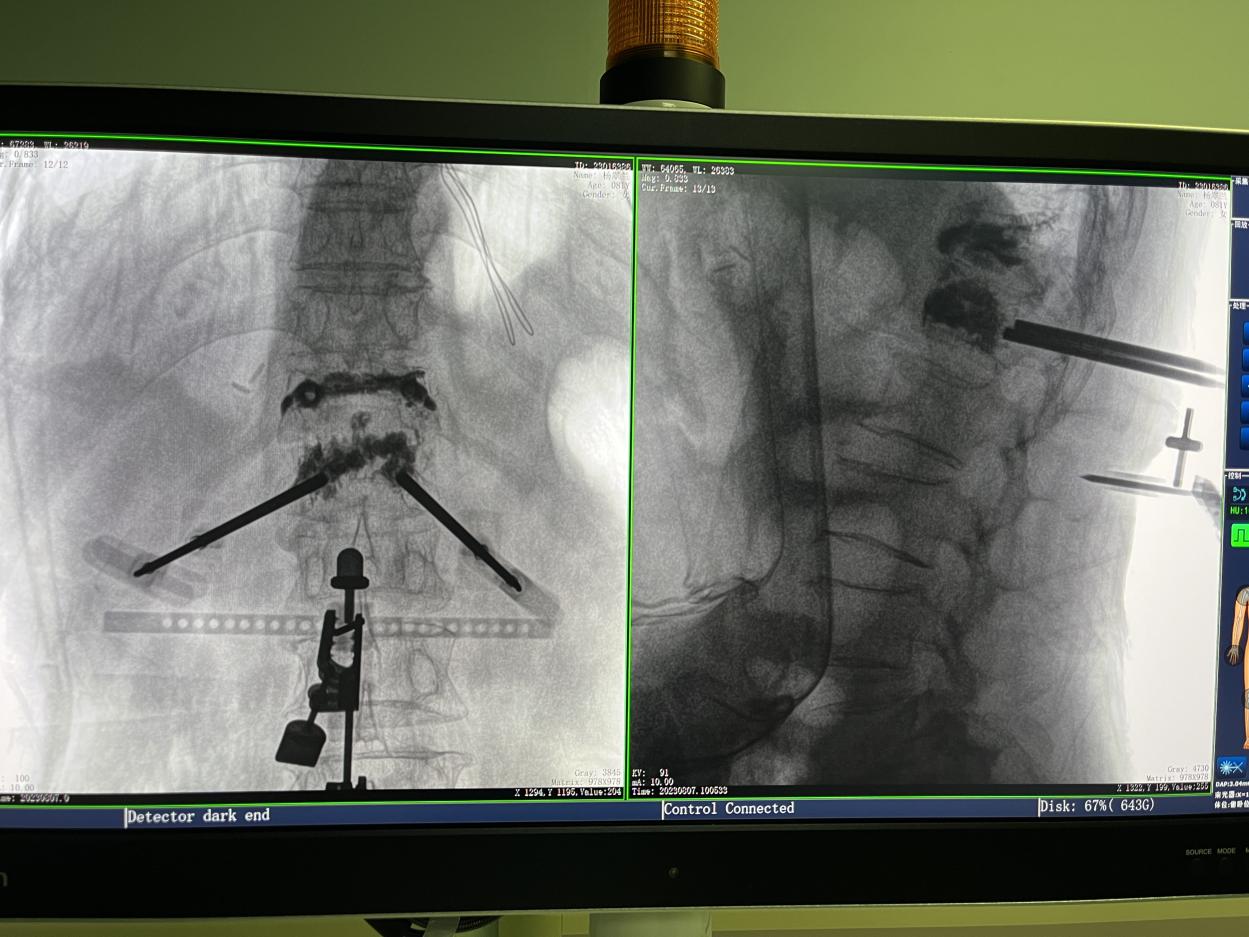

傳統的開放式手術需暴露手術可見視野,以便醫生獲得更多的判斷信息,手術創口大,術后恢復時間長。而在骨科機器人輔助的微創手術中,手術創口僅為1~2厘米左右的小切口,創傷小、恢復快。

骨科機器人手術-術后影像